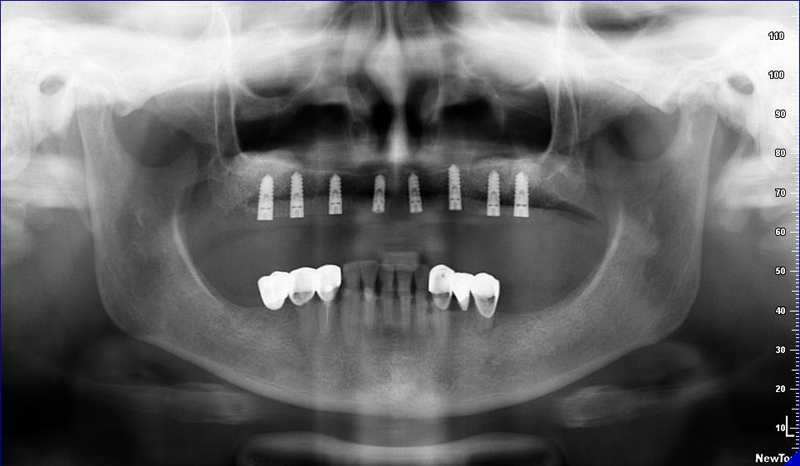

8) Kontrolní RTG snímek po operaci